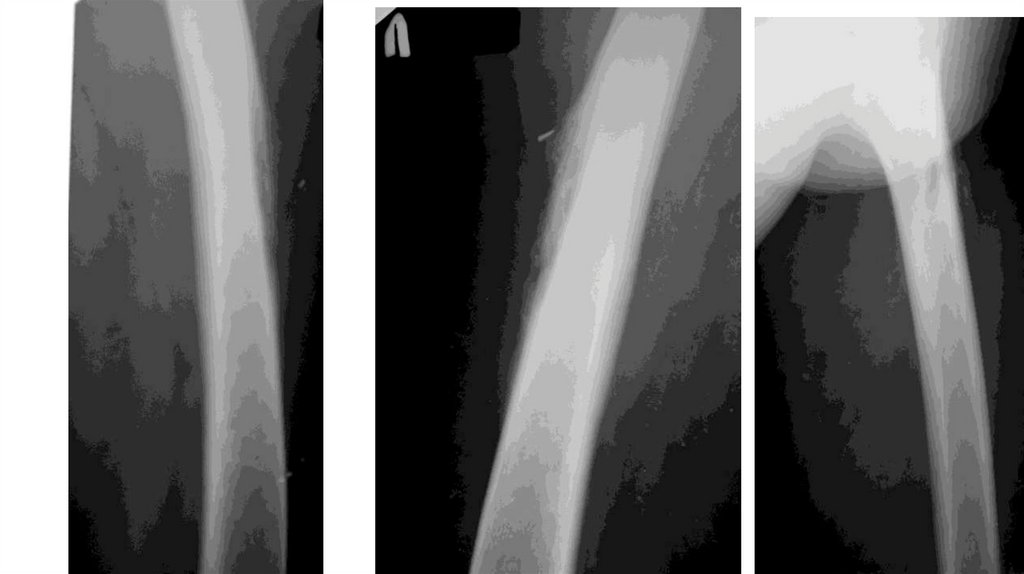

Воспалительные заболевания опорнодвигательного аппарата

«Воспалительные

заболевания опорнодвигательного аппарата»